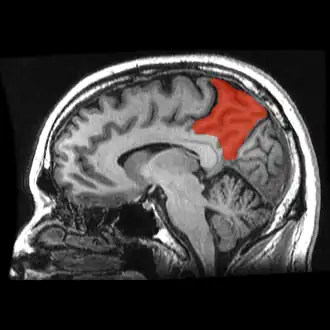

Corte de una IRM sagital mostrando el precúneo en rojo. | ||

Se denomina precuña o precúneo a una parte del lóbulo parietal superior oculto en la fisura longitudinal medial entre los dos hemisferios cerebrales. A veces se describe como la zona media de la corteza parietal superior. El precúneo está limitado anteriormente por la rama marginal del surco cingulado, posteriormente por el surco parietooccipital, e inferiormente por el surco subparietal. Está involucrado con la memoria episódica, procesamiento visuoespacial, reflexiones sobre uno mismo, y aspectos de la conciencia.

El precúneo es una pequeña circunvolución en forma de cuña en la superficie medial del lóbulo parietal del cerebro, delimitada posteriormente por el surco parietooccipital y anteriormente por el lóbulo paracentral.